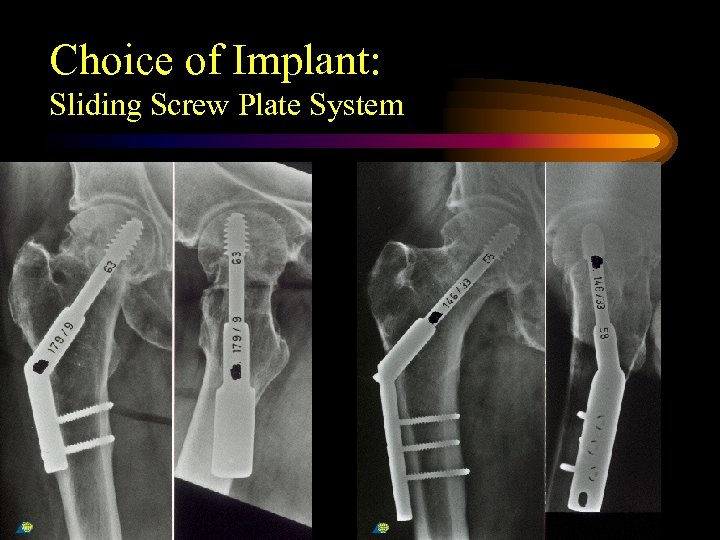

Choice of Implant: Sliding Screw Plate System

Choice of Implant: Sliding Screw Plate System

Choice of Implant Benterud JG, Husby T, Nordsletten L, Alho A: “Fixation of displaced femoral neck fractures with a sliding screw plate and a cancellous screw or two Olmed screws. A prospective study of 225 elderly patients with a 3 -year follow up”. Ann Chir Gynaecol 1997; 86 (4) 338 -42

Choice of Implant Benterud JG, Husby T, Nordsletten L, Alho A: “Fixation of displaced femoral neck fractures with a sliding screw plate and a cancellous screw or two Olmed screws. A prospective study of 225 elderly patients with a 3 -year follow up”. Ann Chir Gynaecol 1997; 86 (4) 338 -42

Choice of Implant Ann Chir Gynaecol 1997; 86 (4) 338 -42 Conclusions. Both treatment methods resulted in high rate of osteofixation failures (18. 5 % in the SSP group and 19. 5 % in the Olmed group) and non-unions (6. 2 % and 8. 5% respectively)

Choice of Implant Ann Chir Gynaecol 1997; 86 (4) 338 -42 Conclusions. Both treatment methods resulted in high rate of osteofixation failures (18. 5 % in the SSP group and 19. 5 % in the Olmed group) and non-unions (6. 2 % and 8. 5% respectively)

Choice of Implant • In 31 - B 2 fractures of the “young geriatric” patient a 4 hole DHS with an antirotational screw, however, is the implant of choice. The fixation on the tensile side of the femur and gliding cylinder for the screw provides stability over time

Choice of Implant • In 31 - B 2 fractures of the “young geriatric” patient a 4 hole DHS with an antirotational screw, however, is the implant of choice. The fixation on the tensile side of the femur and gliding cylinder for the screw provides stability over time